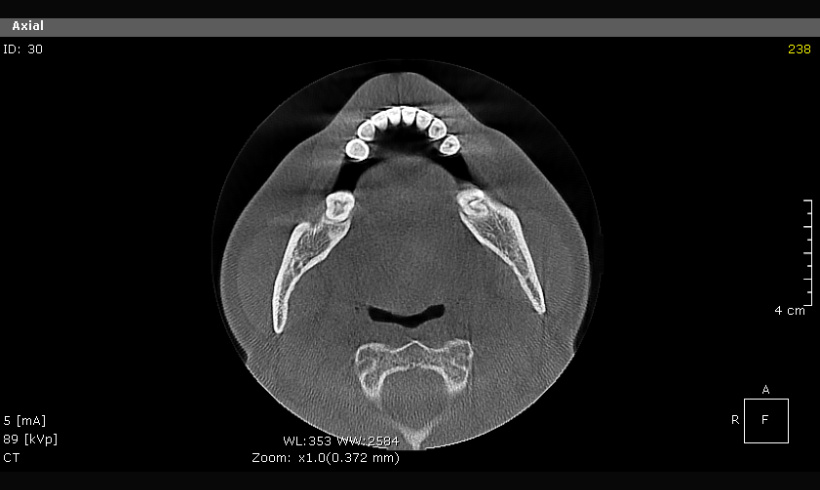

La tomografía, junto con el escaneo nos permite realizar guías quirúrgicas para la colocación de implantes, alargamiento de coronas, colocación de mini implantes de ortodoncia, tratar endodóndicamente dientes calcificados.

Tomografía para guías quirúrgicas